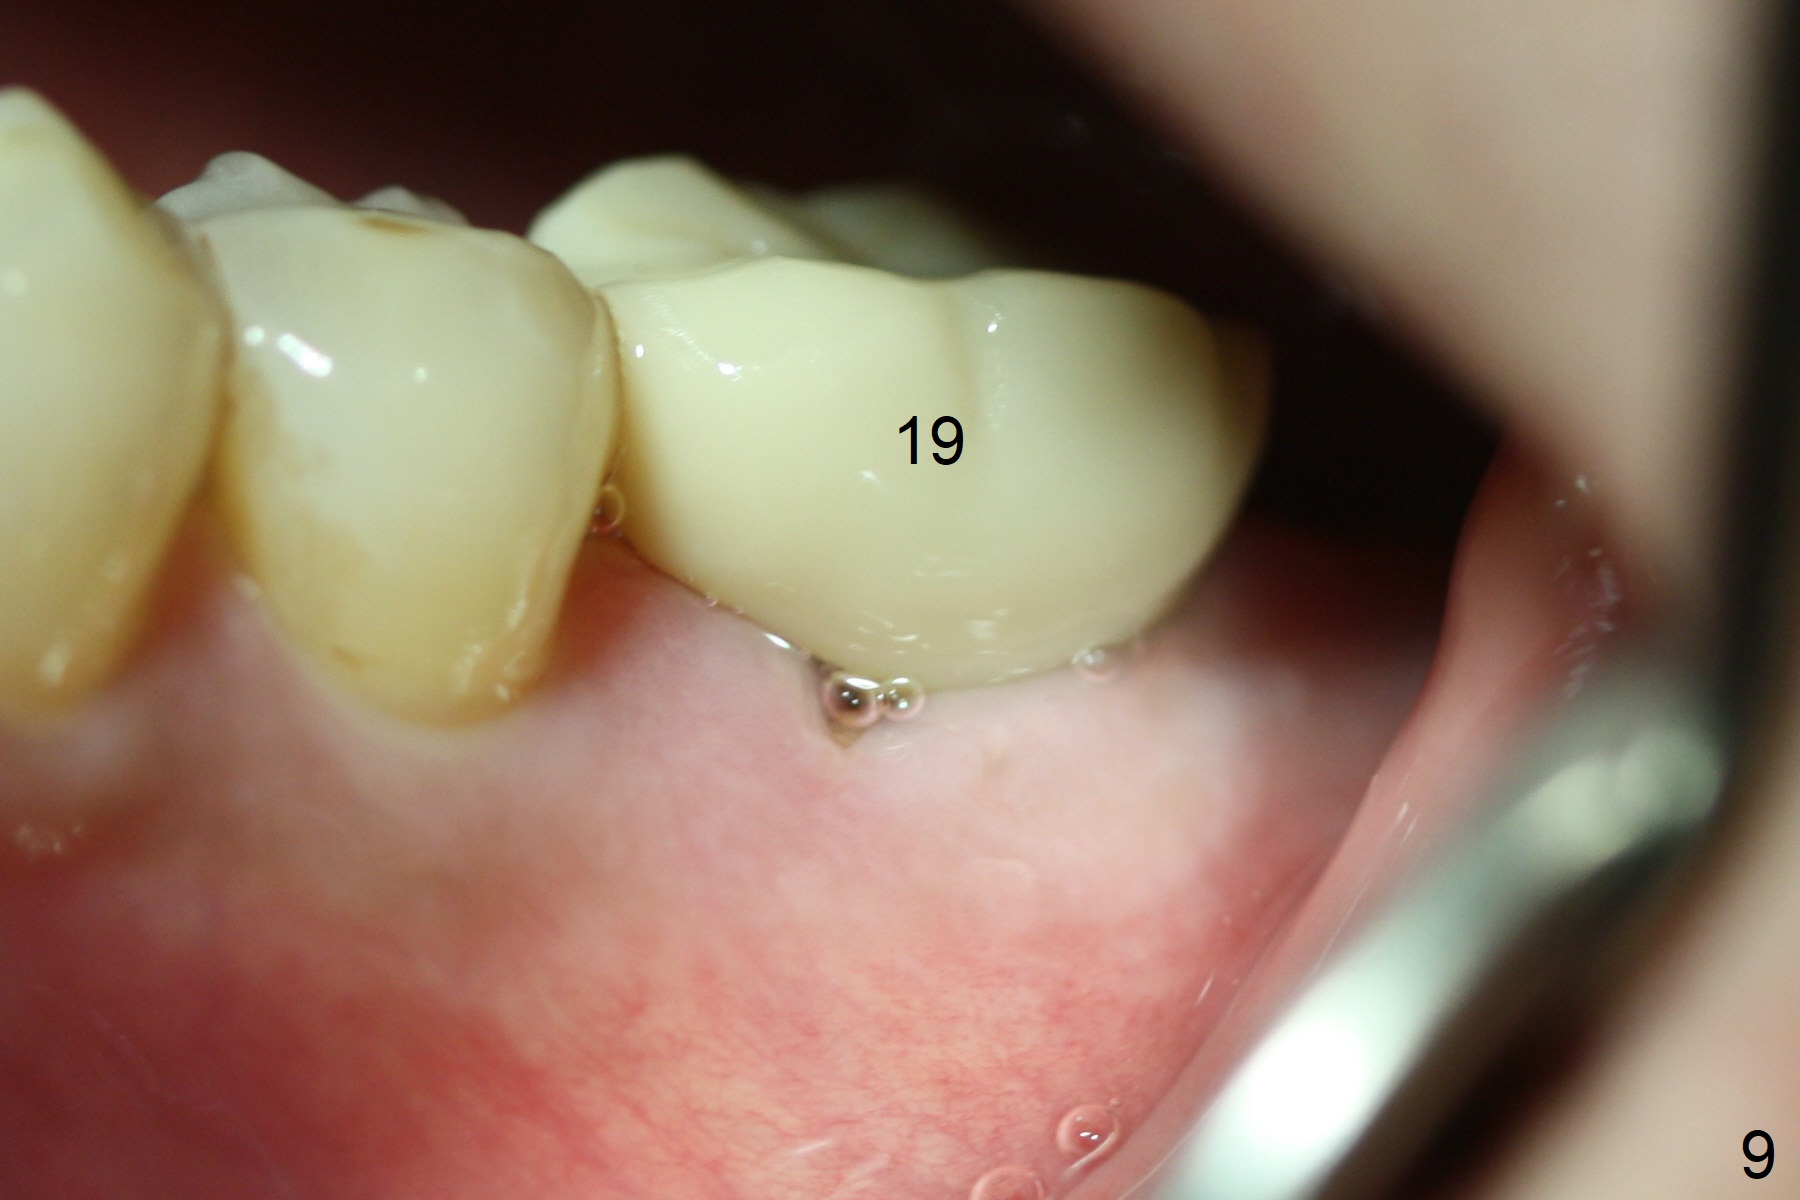

Due to severe furca (Fig.1 *) and distal root (Fig.2 D) infection at #31, there is pain when osteotomy is initiated in the apical native bone for 2 mm after extraction (Fig.3). The distal root is found to have vertical fracture. Socket preservation is performed with Vera Graft, collagen plug and 6-month membrane (Fig.4). In fact it would be possible to initiate osteotomy (Fig.5 white line) in the mesial slope (red dashed line) for implant placement (less infection (far from the lesion), less pain). There is postop pain and swelling, but the symptoms are less 7 days postop (Fig.6). The patient returns 6 months post socket preservation (Fig.7). The bone density at the healed socket is high (>1000 units); a 5x10 mm implant will be placed with guide (Fig.8). After implant placement at #18, make a buccal incision to explore the buccal gingival defect at #19 (Fig.9, 1), most likely due to extra bone graft.